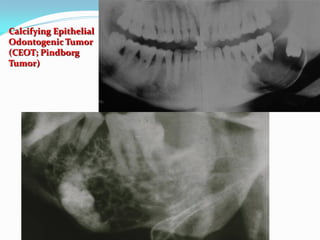

Calcifying Epithelial Odontogenic Tumor

(CEOT; Pindborg Tumor)

 Pindborg tumor accounts for < 1 % of all odontogenic

tumors.

 It is clearly of odontogenic origin but its histogenesis is

uncertain.

 The tumor cells are said to resemble cells of the

CEOT

 This tumor forms an amorphous



material

that is said to be amyloid or

amyloid-like

Whatever it is, it calcifies in a

concentrically lamellated

“tree-ring” pattern calcifications.

This explains the name of

calcifying epithelial odontogenic

tumor.

tumor in the body of the mandible. It

appears as a radiolucent lesion with

smokey dense areas.

CEOT: Radiographic Features

 CEOTs occur as radiolucent lesions with/without

opaque foci.

 They are usually well-circumscribed and may be

unilocular or multilocular.

 Slightly over 50 % of the CEOTs are associated with an

unerupted tooth.